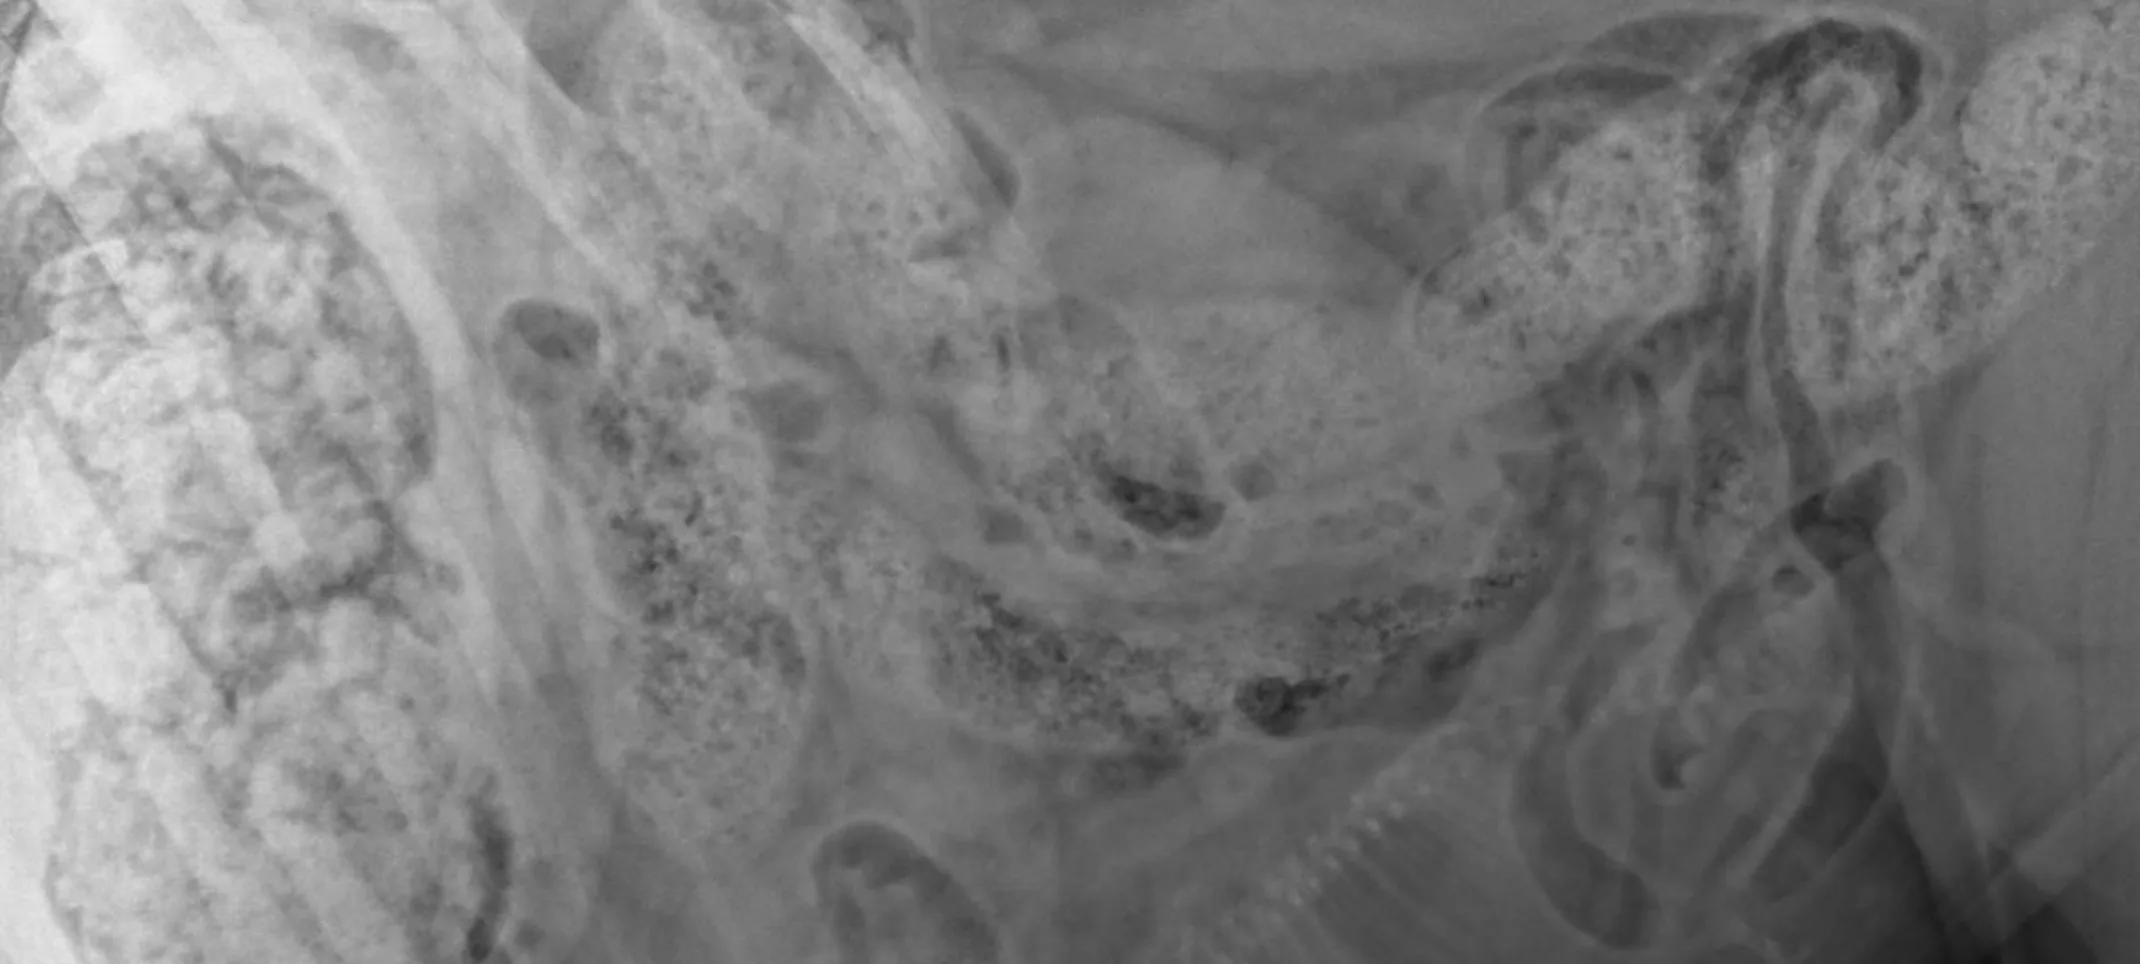

Radiography, also known as X-rays, is one of the most common and valuable medical diagnostic tools. X-rays are highly useful for screening areas of the body that have contrasting tissue densities, or when evaluating solid tissues.

X-rays can be used to detect a variety of ailments in animals including arthritis, tumors, bladder and kidney stones, heart diseases, and lung abnormalities such as pneumonia. They are also used to evaluate bone damage, the gastrointestinal tract, respiratory tract, genitourinary system, organ integrity, and even identify foreign objects that may have been ingested. Dental radiographs help distinguish healthy teeth from those that may need to be extracted and identify any abnormalities beneath the gums including root damage, tumours, and abscesses. In some cases, we may need to sedate your pet or use short-acting general anesthesia.